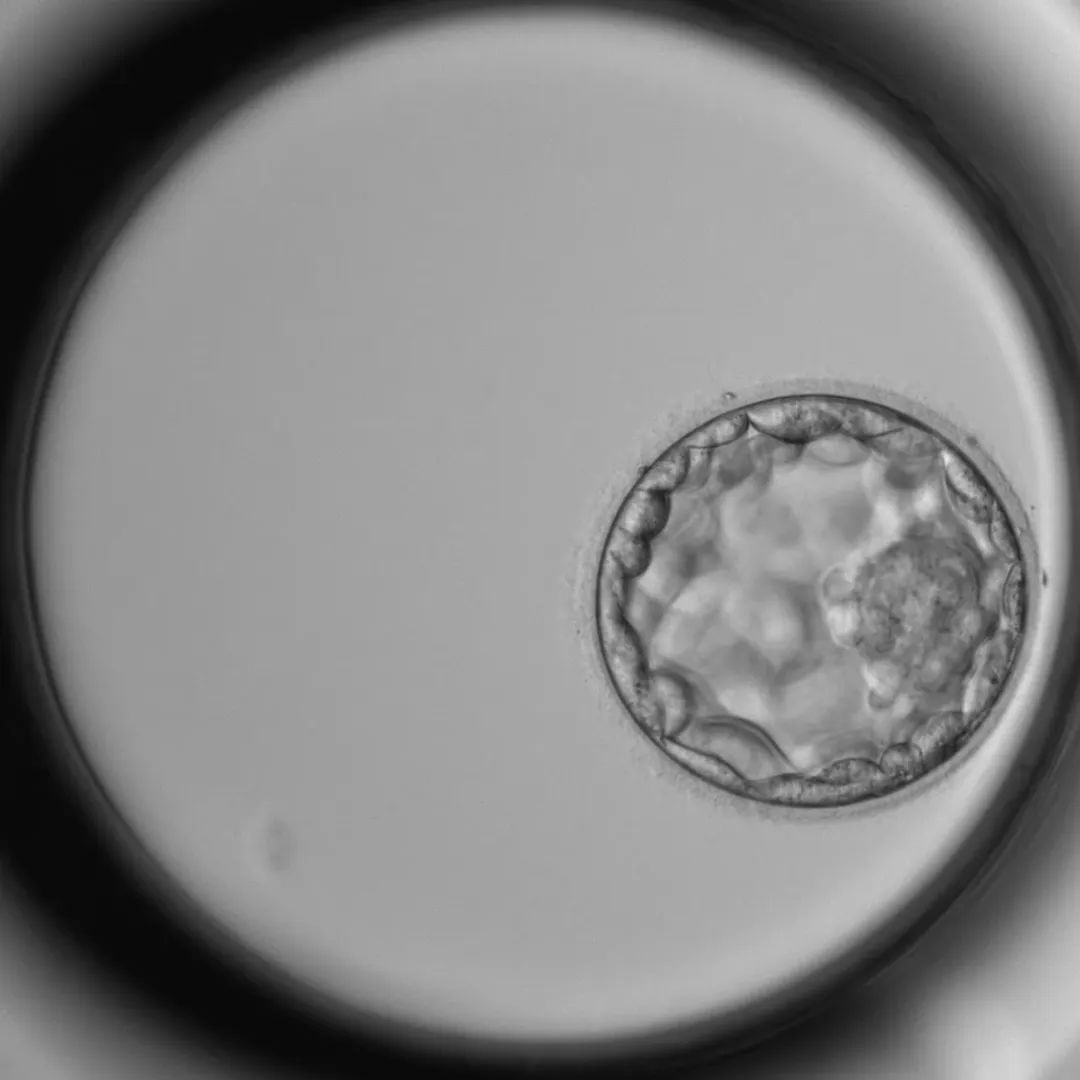

看着已经在培养箱中孕育的胚胎,高博士知道,等待它们的最终考验就在不远处——在生殖实验室里有一套完整的评分系统,这套评分系统,严苛地将胚胎分为多个等级,决定着它们能否获得“子宫入场券”。

很快,一个各方面都表现得相当优秀的胚胎,被高博士一眼相中,等待着被移植的命运。